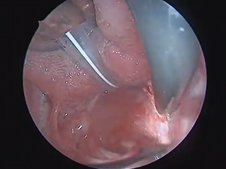

Microdirect Laryngoscopy and CO2 Laser Total Vestibulectomy for Pyolaryngocele

- Date : 01/01/2020